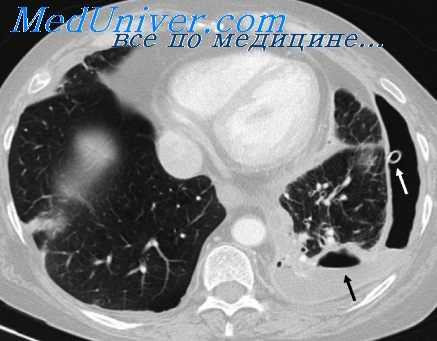

Заполнение бронхов контрастным веществом при исследовании больного на трохоскопе производится, как и при обычной методике, после поворота больного на бок. Однако в данном случае нет необходимости применять боковую бронхограмму, располагая рентгеновскую пленку с противоположной исследуемой стороны.

Надувные манжетки, изолирующие дыхательные пути каждого легкого, исключают затекание контрастного вещества во время исследования в бронхи второго легкого. Благодаря этому, заполнив бронхи нижележащего легкого, мы поворачиваем больного на спину и производим бронхографию в прямой проекции. Затем под контролем экрана совершаем поворот больного в боковое положение, при котором исследуемое легкое становится вышележащим, то есть максимально приближенным к рентгеновской пленке. В этом положении осуществляют боковую бронхограмму.

30 больным, исследованным по данной методике, мы производили две боковые бронхограммы: первая — со стороны, противоположной исследуемому легкому, иначе говоря, по общепринятой методике, и вторая — со стороны исследуемого легкого.